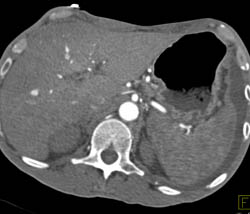

Gastric Cancer